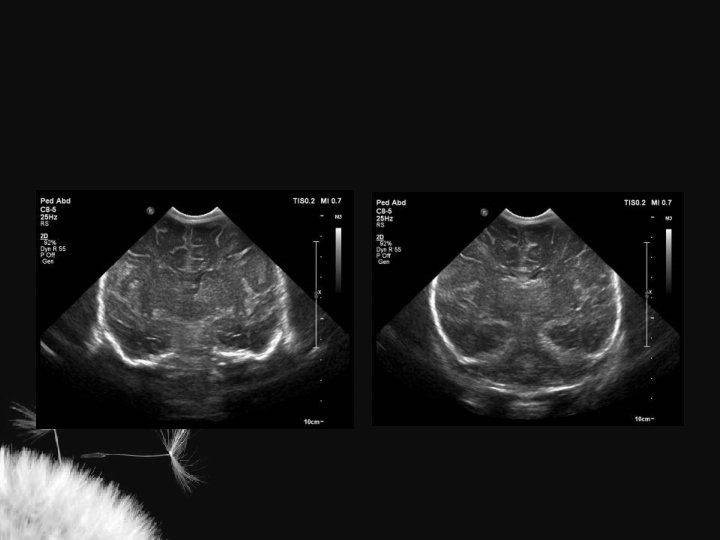

Macrocrania • Macrocrania benigna hidrocefalia benigna da infância, coleção extra axial benigna da infância • Condições patológicas: • US – Coleções anecóicas – Formato em V – Sulcos e giros proeminentes – Ventrículos normais ou proeminentes – Pia-aracnoide com ecogenicidade normal – Higroma subdural – Hematoma subdural – Abscesso secundário a meningite – Coleções ecogênicas – Formato em U – Sulcos e giros deslocados ou achatados – Ventrículos alargados – Pia-aracnoide hiperecogênica

Hidrocefalia benigna da infância – sinal da veia cortical positivo

Coleção subdural – sinal da veia cortical negativo